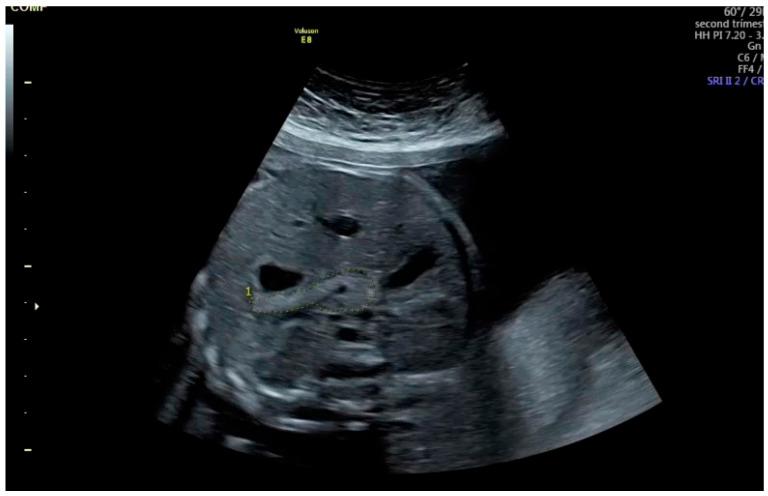

The objective of this study was to investigate the relationship between the simultaneous 75 g Oral glucose tolerance test (OGTT), gestational diabetes mellitus (GDM), and fetal pancreatic circumference at 24-28 weeks of gestation. This prospective case-control study was conducted between September 2024 and February 2025 at our perinatology clinic, which provides tertiary health care services. The correlation between the 75 g OGTT, GDM, and pancreatic circumference was assessed by comparing fetal pancreatic circumference between the groups with and without GDM at the time of diagnosis. A total of 130 pregnant patients were recruited for this` study, with 64 patients forming the GDM group and 66 patients forming the control group. Fetal pancreas circumference (7.0 cm vs. 6.4 cm, < 0.001), fetal pancreas circumference percentile (88.5 vs. 52, < 0.001), and the rate of fetal pancreas size >90th percentile (15.6% vs. 3%, < 0.001) were significantly higher in the GDM group compared to the control group. Although our findings demonstrate a statistically significant correlation between fetal pancreatic circumference and GDM, diagnostic performance remains modest. Therefore, fetal pancreatic circumference should be interpreted as a supportive marker, such as family history, rather than a definitive marker for identifying individuals at risk for GDM.

本研究的目的是调查妊娠24 - 28周时同步进行的75克口服葡萄糖耐量试验(OGTT)、妊娠期糖尿病(GDM)与胎儿胰腺周长之间的关系。这项前瞻性病例对照研究于2024年9月至2025年2月在我们提供三级医疗保健服务的围产医学诊所进行。通过比较诊断时患有和未患有GDM的两组胎儿胰腺周长,评估75克OGTT、GDM与胰腺周长之间的相关性。本研究共招募了130名孕妇,其中64名患者组成GDM组,66名患者组成对照组。GDM组的胎儿胰腺周长(7.0厘米对6.4厘米,<0.001)、胎儿胰腺周长百分位数(88.5对52,<0.001)以及胎儿胰腺大小>第90百分位数的比例(15.6%对3%,<0.001)均显著高于对照组。尽管我们的研究结果表明胎儿胰腺周长与GDM之间存在统计学上的显著相关性,但诊断性能仍然一般。因此,胎儿胰腺周长应被解释为一种辅助标志物,如家族史,而不是用于识别GDM风险个体的确定性标志物。